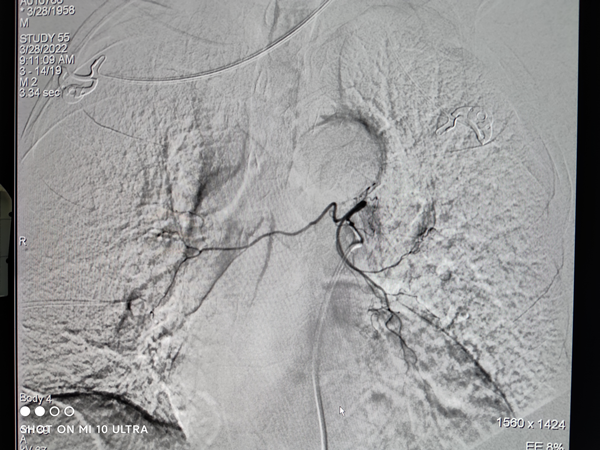

对张先生的病症,彭齐荣教授团队医生经过仔细会诊,详细研究了张先生的PET/CT检查报告后,给出了动脉灌注栓塞+微波消融+中医调理的综合治疗方案。

彭齐荣教授指出,张先生肺部的肿瘤已经是恶性肿瘤了,为了更好的治疗,应该对不同阶段制定不同的治疗方案。针对肿瘤的局部治疗,医生给予了两个治疗方案:

将动脉灌注、动脉栓塞与微波消融治疗相结合,对肿瘤病灶进行精准治疗,同时,针对全身调理,特别邀请了肿瘤中医治疗专家徐伯平教授前来会诊,为张先生安排补中益气、增强免疫力、补气健脾、除痰散结的全身调养。